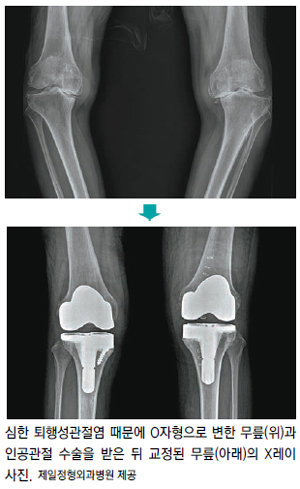

이때 증세가 심하지 않으면 약물이나 물리치료, 운동요법 등으로 치료한다. 이런 보존적 치료로 효과가 없고, 연골이 닳아 통증이 심해져 일상생활에 지장을 받거나 ‘O’자 다리로 변형까지 진행된 말기 퇴행성관절염 환자들은 인공관절 수술을 고려해야 한다.

최 원장은 “인공관절 수술은 심하게 손상돼 치료가 불가능한 연골을 제거하고, 금속과 강화 플라스틱으로 된 인공관절로 교체하는 것으로만 알려져 있다”며 “하지만 손상된 무릎이 정상적인 운동범위를 되찾을 수 있도록 세밀한 과정이 필요하다. 이때 필요한 기술이 연부조직 균형 맞추기”라고 말했다.